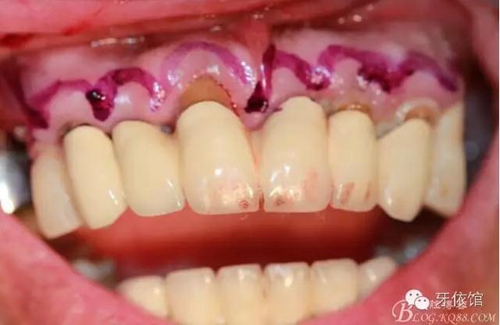

術(shù)中口內(nèi)照

降低骨高度,左右1,2骨寬度嚴(yán)重不足,決定將前牙2——2區(qū)間植體植在切牙孔內(nèi)

左右3牙位分別植入一顆